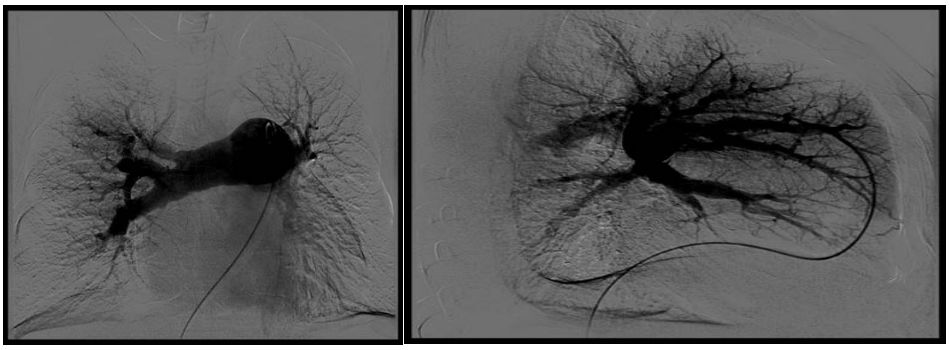

患者入院后肺动脉造影显示:双侧肺动脉多发狭窄,闭塞,主肺动脉增宽。